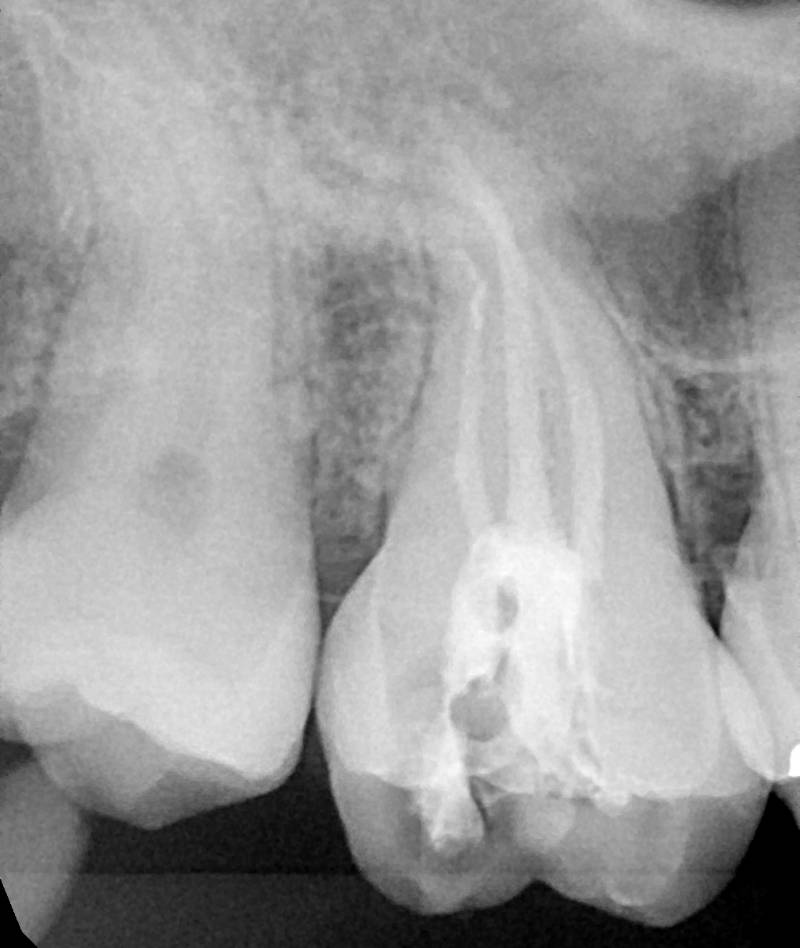

L’endodonzia (devitalizzazione dei denti) è alla base di ogni lavoro protesico e richiede una perfetta esecuzione, poiché un’endodonzia mal fatta causa granulomi e ascessi con la perdita dei denti e di tutto il lavoro protesico eseguito sull’elemento, con costi biologici ed economici gravi

Nel nostro studio l’endodontista utilizza strumenti in Nichel-Titanio (M2 di Sweden & Martina) e tecniche di ultima generazione (strumenti rotanti, radiografia digitale ad ogni step e ingrandimenti ottici) che garantiscono la perfetta riuscita del trattamento.